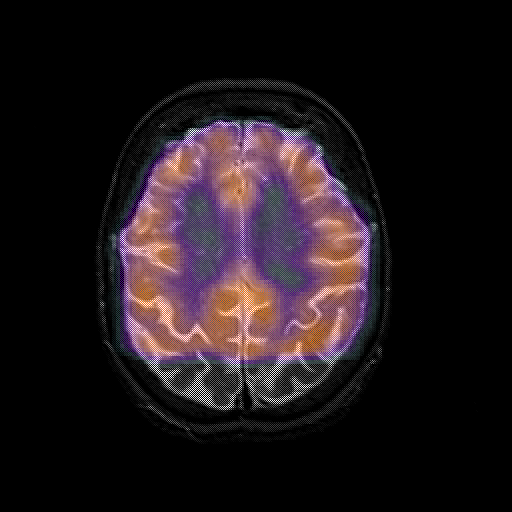

overlay 1: Slice 38

Slice 38

MRCBFCBF with

T1PDT2T1PDT2